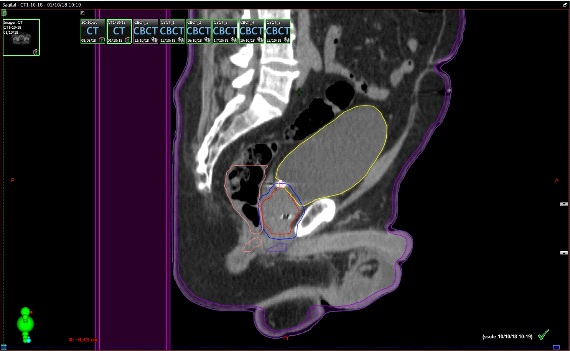

Fig. 3. Técnica de Radioterapia IGRT (Guiada por imágenes). Derecha: TAC de simulación con contornos: Rojo CTV: clinic target volume(próstata y vesículas seminales); Azul: PTV: patologic target volume); Amarillo: Vejiga (OAR); Rosado: Recto (OAR); Verde: Cadera derecha (OAR); Celeste: Cadera izquierda (OAR). Izquierda: Conbeam en máquina de tratamiento, en donde la imagen en el aceleradorse superpone con los contornos hecho en el TAC de simulación.